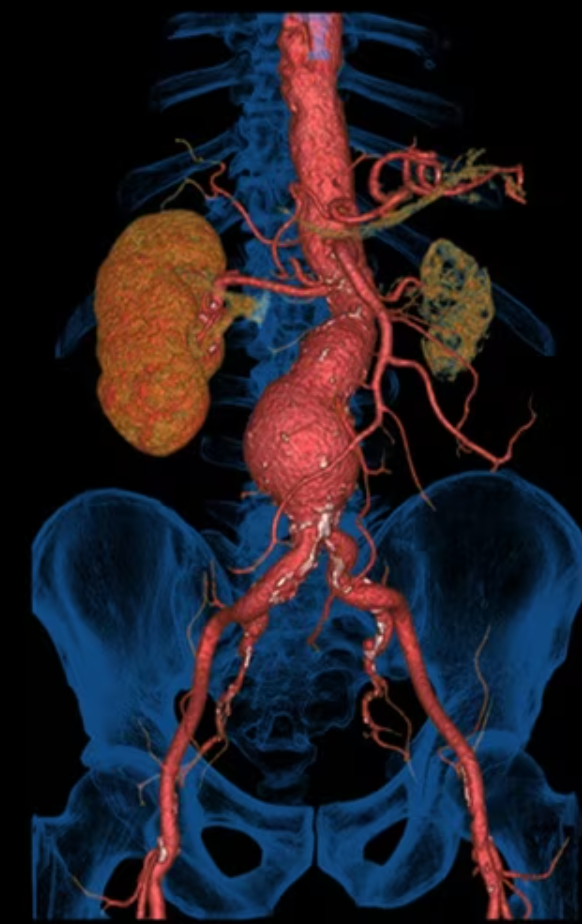

Revolution Maxima включает набор специализированных клинических решений, предназначенных для выполнения различных типов КТ-исследований. Благодаря реконструкции с матрицей 1024 × 1024 формируются изображения высокого разрешения, на которых хорошо различимы мелкие анатомические структуры. Это важно при ангиографических исследованиях, оценке коронарных артерий, сосудов шеи и периферических артерий.